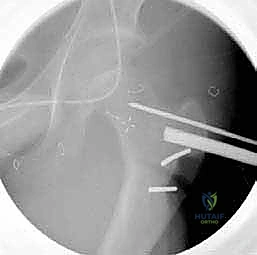

3. إدخال السلك الدليلي (Guide Wire)

تحت توجيه الأشعة السينية المباشرة داخل غرفة العمليات (C-arm)، يقوم الدكتور هطيف بإدخال سلك دليلي في عنق ورأس عظم الفخذ بالزاوية الصحيحة والمحسوبة بدقة.

4. القطع العظمي (The Osteotomy)

باستخدام منشار جراحي دقيق جداً وعالي السرعة، يتم إجراء قطع عرضي في عظم الفخذ في المنطقة المحددة. هذه الخطوة تفصل الجزء العلوي (الرأس والعنق) عن الجزء السفلي (جسم العظم).